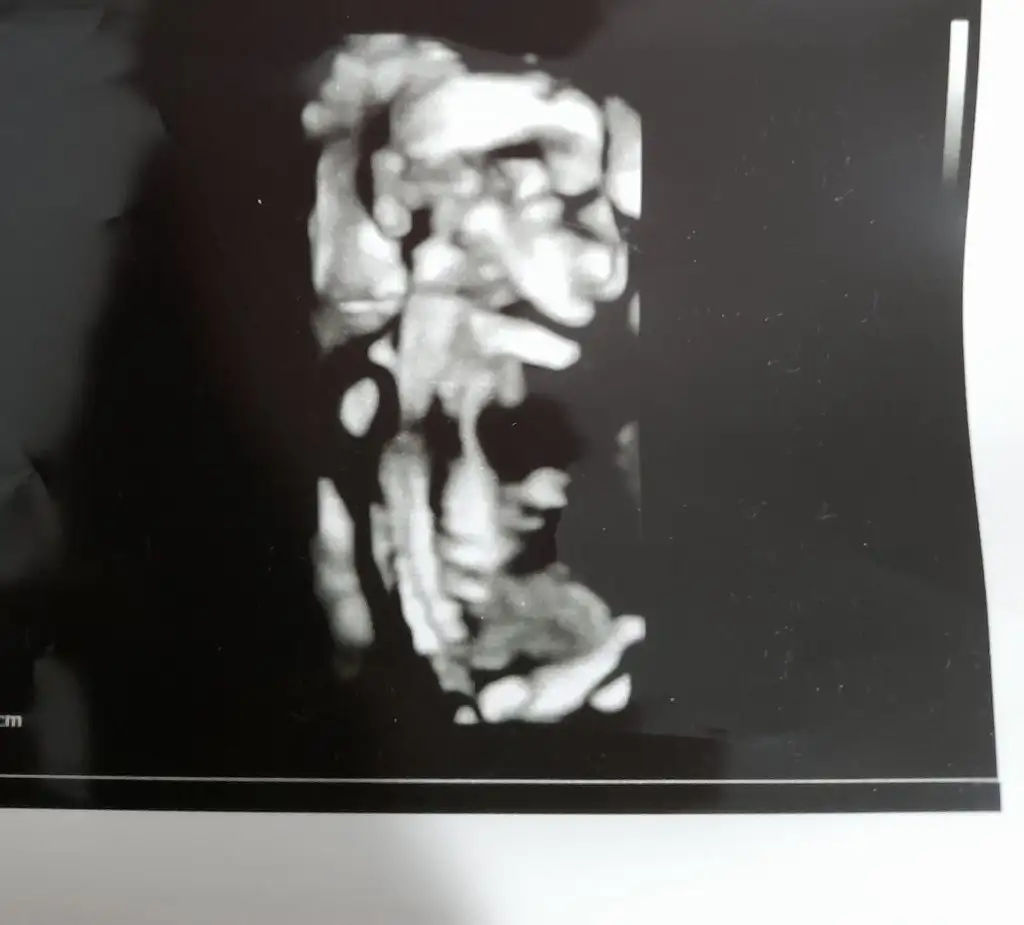

Adet olarak hesaplama da 8 haftalık ama doktor 9+3 dedi burda bakarmısınız 🙏🙏🙏🙏

Merhabaaalarrr Lütfen bana da bakabilirmiainiz Sevgili Ikra Meyra🙏